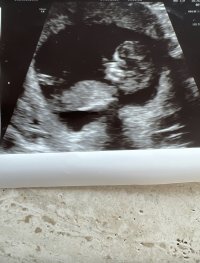

På grunn av vinkelen på rumpa så er jeg litt usikker her om jeg får vinkelen riktig, men det ser jentete ut. Hvis du deler den på nubqueens på facebook så kan de svare med større sikkerhet på denne tror jegVis vedlegget 417058